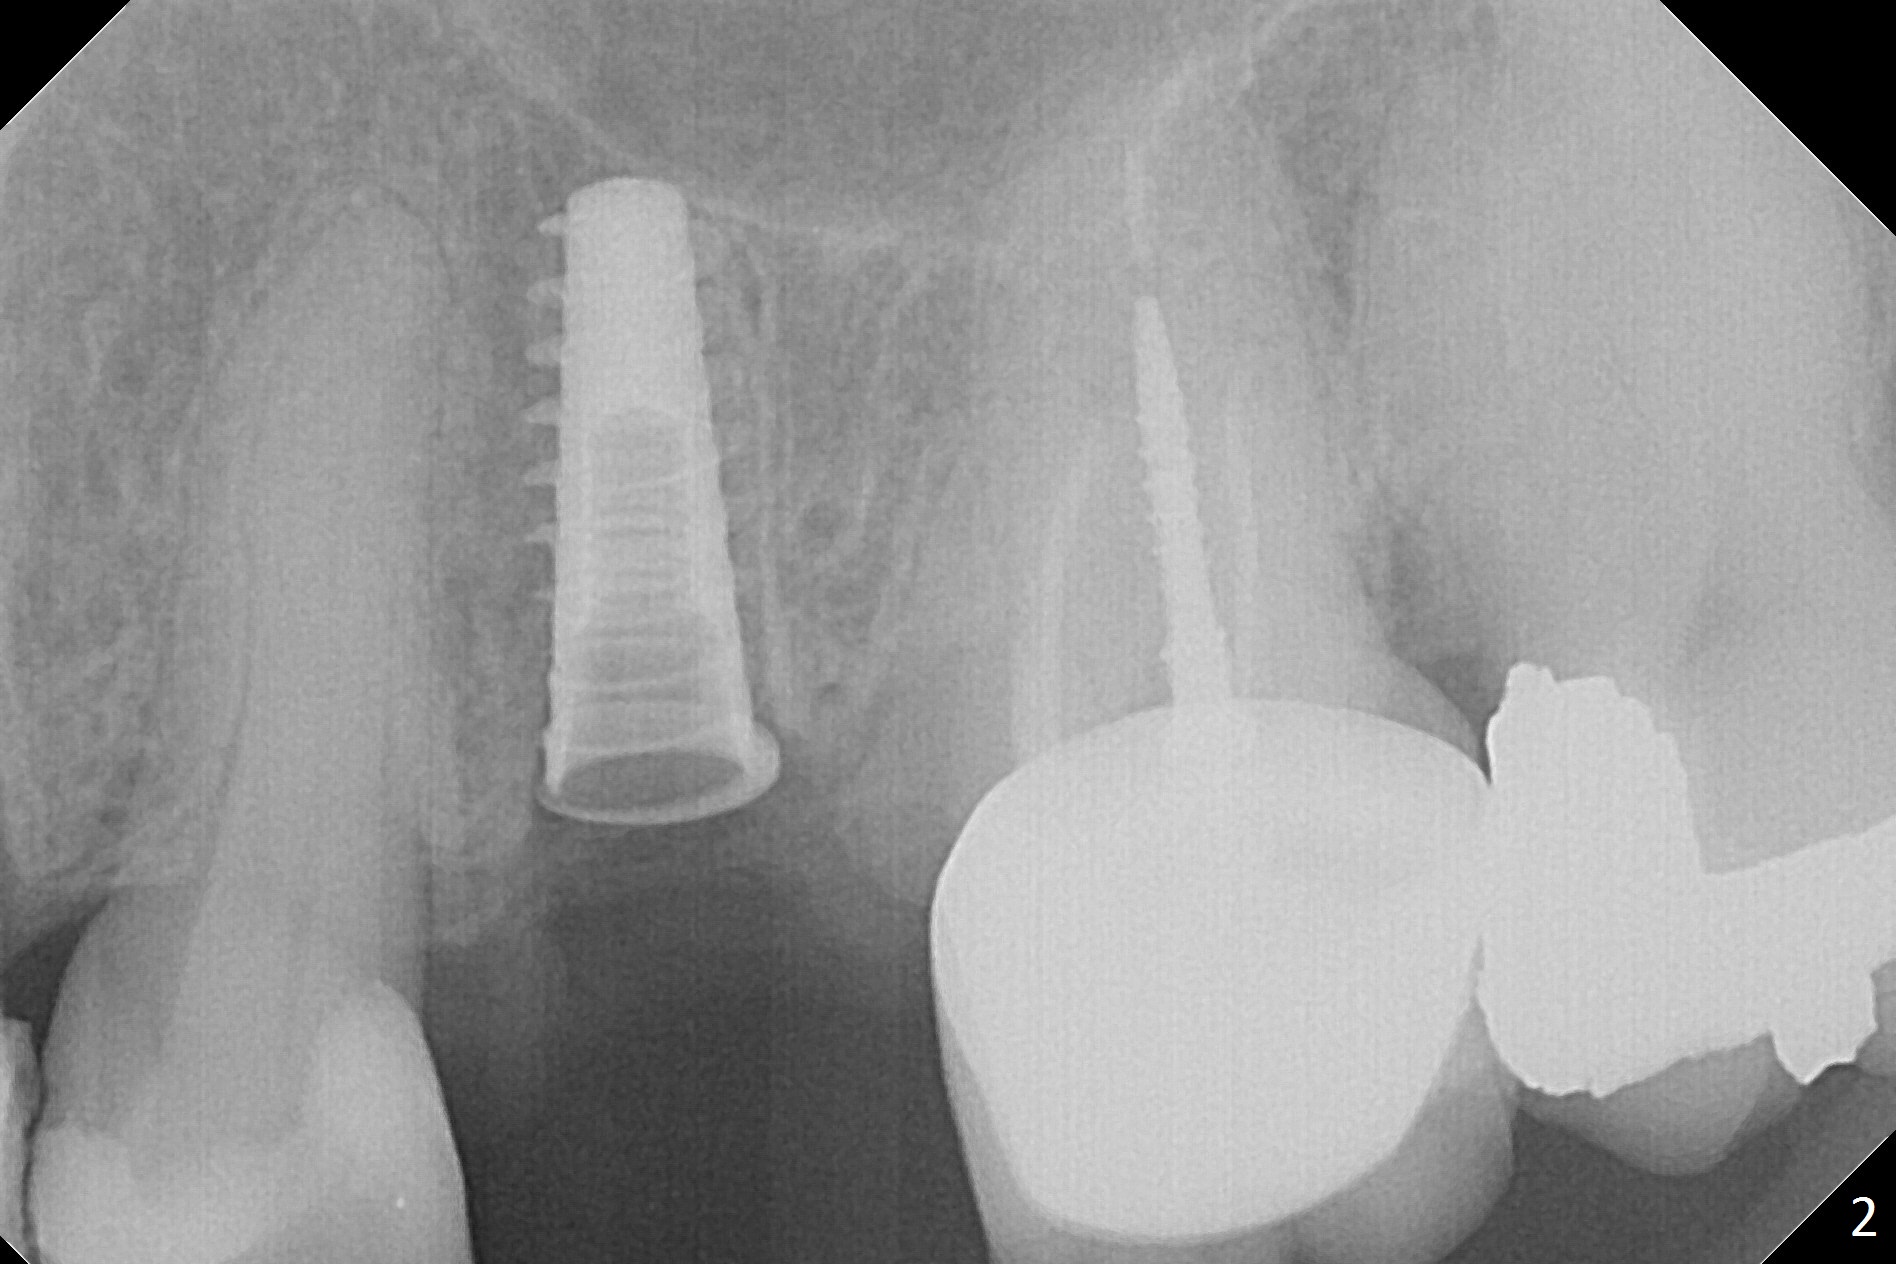

Since the apical native bone is limited at #13 after extraction, no PA is taken until a 4x11 mm dummy implant is placed after 1.6 mm and 3.3 mm drills for 13 mm (Fig.1). After using Lindamann bur to move the osteotomy distal and reusing 3.3 mm drill, the trajectory of a 4.5x11 mm IBS dummy implant improves (Fig.2,3 with low stability). When the implant is removed, the buccal portion of the socket is found to be perforated (Fig.4 P). Although the reason for the perforation is unknown, it is repaired by insertion of a piece of PRF plug, followed by allograft. #1 and 2 in Fig.4 represent the 1st and 2nd osteotomies, as shown in Fig.1 and 2, respectively. The trajectory of the final 5x13 mm implant is acceptable (Fig.5-7, different angulations), so is insertion torque (45 Ncm). After placing a 5.5x4(4) mm abutment, an immediate provisional is fabricated (Fig.8 P) with occlusal clearance (*). The interdental papillae remain in place 12 days postop (Fig.9 *). There is no sign of postop sinus infection. The provisional is loose 18 days postop; the abutment is changed to 5x4(3) mm (Fig.10). It is difficult to catch the mesial margin of the abutment for impression 4 months postop, due to poor oral hygiene and the short cuff (3 mm, Fig.11). The appointment for impression is rescheduled with emphasis on oral hygiene and no wearing the provisional for a few days prior to next appointment. Bone has grown into the space between the 1st and 2nd threads 5 months post cementation (Fig.12) and the bone is normal, solid and dense 2 years 11 months post cementation (Fig.13 >). There is mesial open margin of the tooth #14 (Fig.13,14 *).